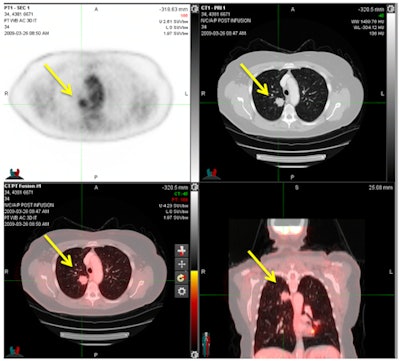

FDG-PET/CT shows a pulmonary metastasis in a cervical cancer patient. PET (upper left), CT (upper right), and PET/CT (bottom row) demonstrate an FDG-avid nodule in the right lower lobe consistent with a pulmonary metastasis and confirmed by histology. Image courtesy of Dr. Michael Gee, PhD.The two readers collectively achieved excellent results in terms of specificity and negative predictive value for both cervical and endometrial distant metastases.

FDG-PET/CT revealed distant metastases in 21 (13.7%) of the cervical cancer patients and in 24 (11.8%) of the endometrial cancer patients. The most common locations for distant metastases among women with cervical cancer were the lungs (5.2%) and the peritoneum (4.6%). Among the endometrial cancer patients, the peritoneum (6.4%) was the most common site for distant metastases.